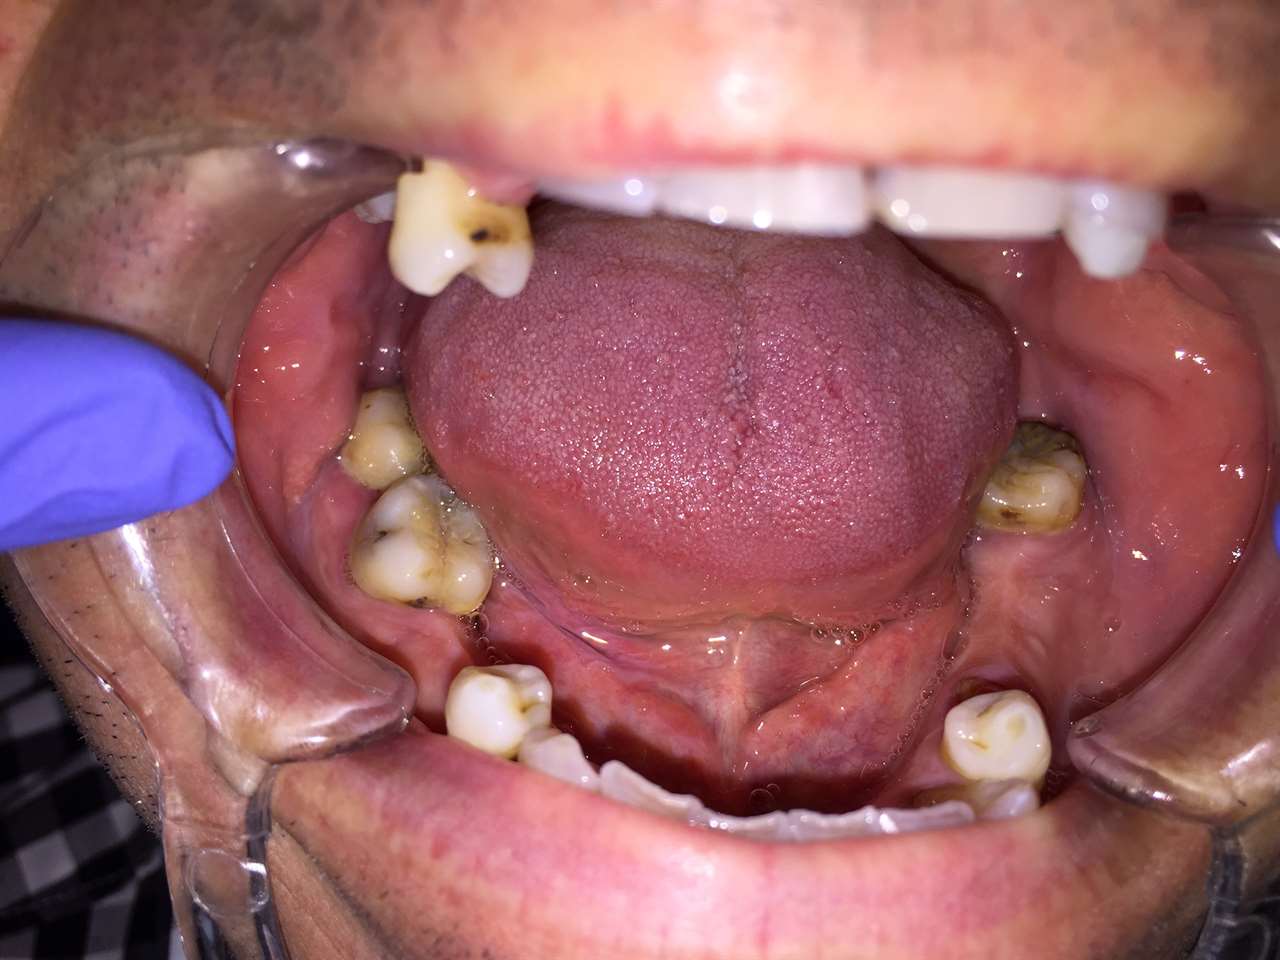

Alsó állcsont teljes rehabilitációja 72 óra alatt

Alsó állcsont teljes rehabilitációja 72 óra alatt, azonnal terhelhető implantátumokkal súlyos paradontitisben szenvedő dohányzó páciens esetében. Az alsó állcsont fogai mind mozogtak az előrehaladott fogágypusztulás miatt.

A fogakat eltávolítottuk, a gyulladt, fertőzött csontot kitakarítottuk, kifertőtlenítettük, majd azonnal implantáltunk.

Svájci, IHDE márkájú, azonnal terhelhető implantátumokat helyzetünk be, és ezekre harmadnapra rögzített, hosszútávú, fémvázas, esztétikus műanyaggal leplezett hidat ragasztottunk be.

Ezt az ideiglenes hidat a sebek gyógyulása miatt használjuk, de tartóssága miatt véglegesként is használható. A legtöbb esetben, ahogy itt is, 6 hónap múlva porcelán hídra cseréljük, a teljes gyógyulás után.